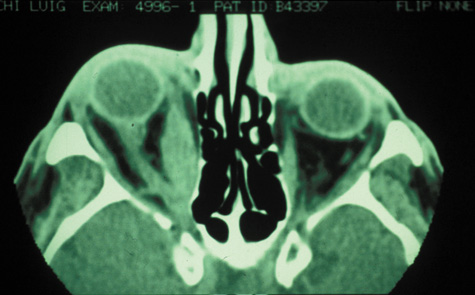

Magnetic resonance imaging (MRI) is purported to be more useful than CT in the diagnosis of preseptal cellulitis. It is less reliable at diagnosing the subtle signs of muscle enlargement and periscleritis and thus is not as useful in differentiating orbital cellulitis from other inflammatory orbital diseases.71 On MRI with gadolinium contrast, orbital cellulitis may show a smearing or linear streaking of the normal fat shadows on T2-weighted images. MRI is excellent for demonstrating localized fluid collections such as abscesses. It is not helpful in distinguishing a transudate from an exudate, because both appear liquid and are of low intensity on T1-weighted images and bright on T2-weighted images (Fig. 19).

Fig. 19. Magnetic resonance image of preseptal cellulitis with anterior abscess formation.

MRI is superior to CT in the diagnosis of cavernous sinus thrombosis. T2- and proton-weighted images show high signal luminal narrowing as well as absent flow or localized parenchymal infarcts (Fig. 20).72 Absent flow can be demonstrated as well in the superior ophthalmic vein in cases of carotid or cavernous sinus thrombosis.72 MRI with gadolinium can help define these abnormalities and can detect dural invasion.

Fig. 20. Cavernous sinus thrombosis. Axial T1 image shows cavernous carotid luminal narrowing on right and enlargement of right cavernous sinus. Note extensive sinus disease.